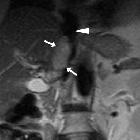

Isolated

intracaval recurrence of resected renal carcinoma. The left renal vein (thin arrows) and infrahepatic vena cava (thick arrows) were homogeneously opacified, without signs of thrombosis. The left kidney showed normal size, parenchymal opacification and contrast excretion, without hydronephrosis.

intracaval recurrence of resected renal carcinoma. Delayed images (c...e): the sizeable, faint filling defect (arrows) in the intrahepatic inferior vena cava persisted in the delayed acquisition. Note metallic clips from previous radical nephrectomy without local recurrence or adenopathies.